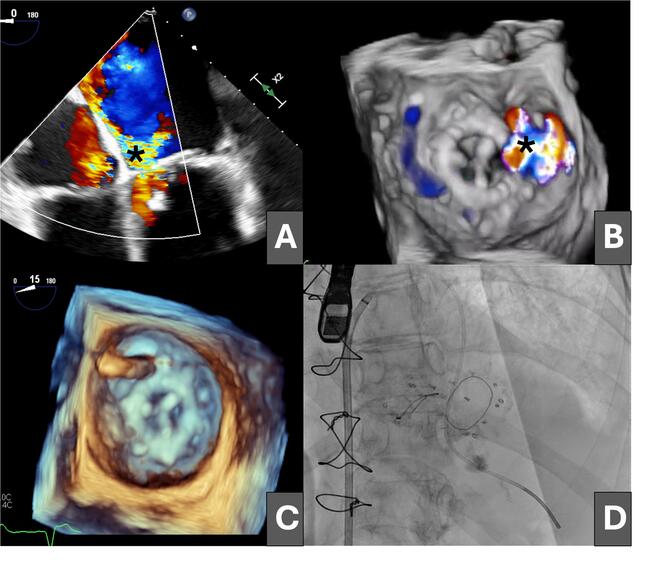

An 81-year-old woman was admitted for heart failure in the context of degenerative valvular disease; she had previously undergone mitral and aortic valve replacement with bioprostheses and tricuspid annuloplasty. The postoperative course was complicated by progressive heart failure and cardiogenic shock secondary to severe mitral regurgitation due to a large anterolateral mitral PVL (Figure 1A and B [asterisk]; Videos 1 and 2).

Having been ruled out for repeat surgery, percutaneous closure of the leak was performed via an initial antegrade approach, crossing the defect from the left atrium with a hydrophilic guidewire (Figure 1C), which was exchanged for a high-support guidewire through a multipurpose catheter advanced into the left ventricle (Figure 1D).